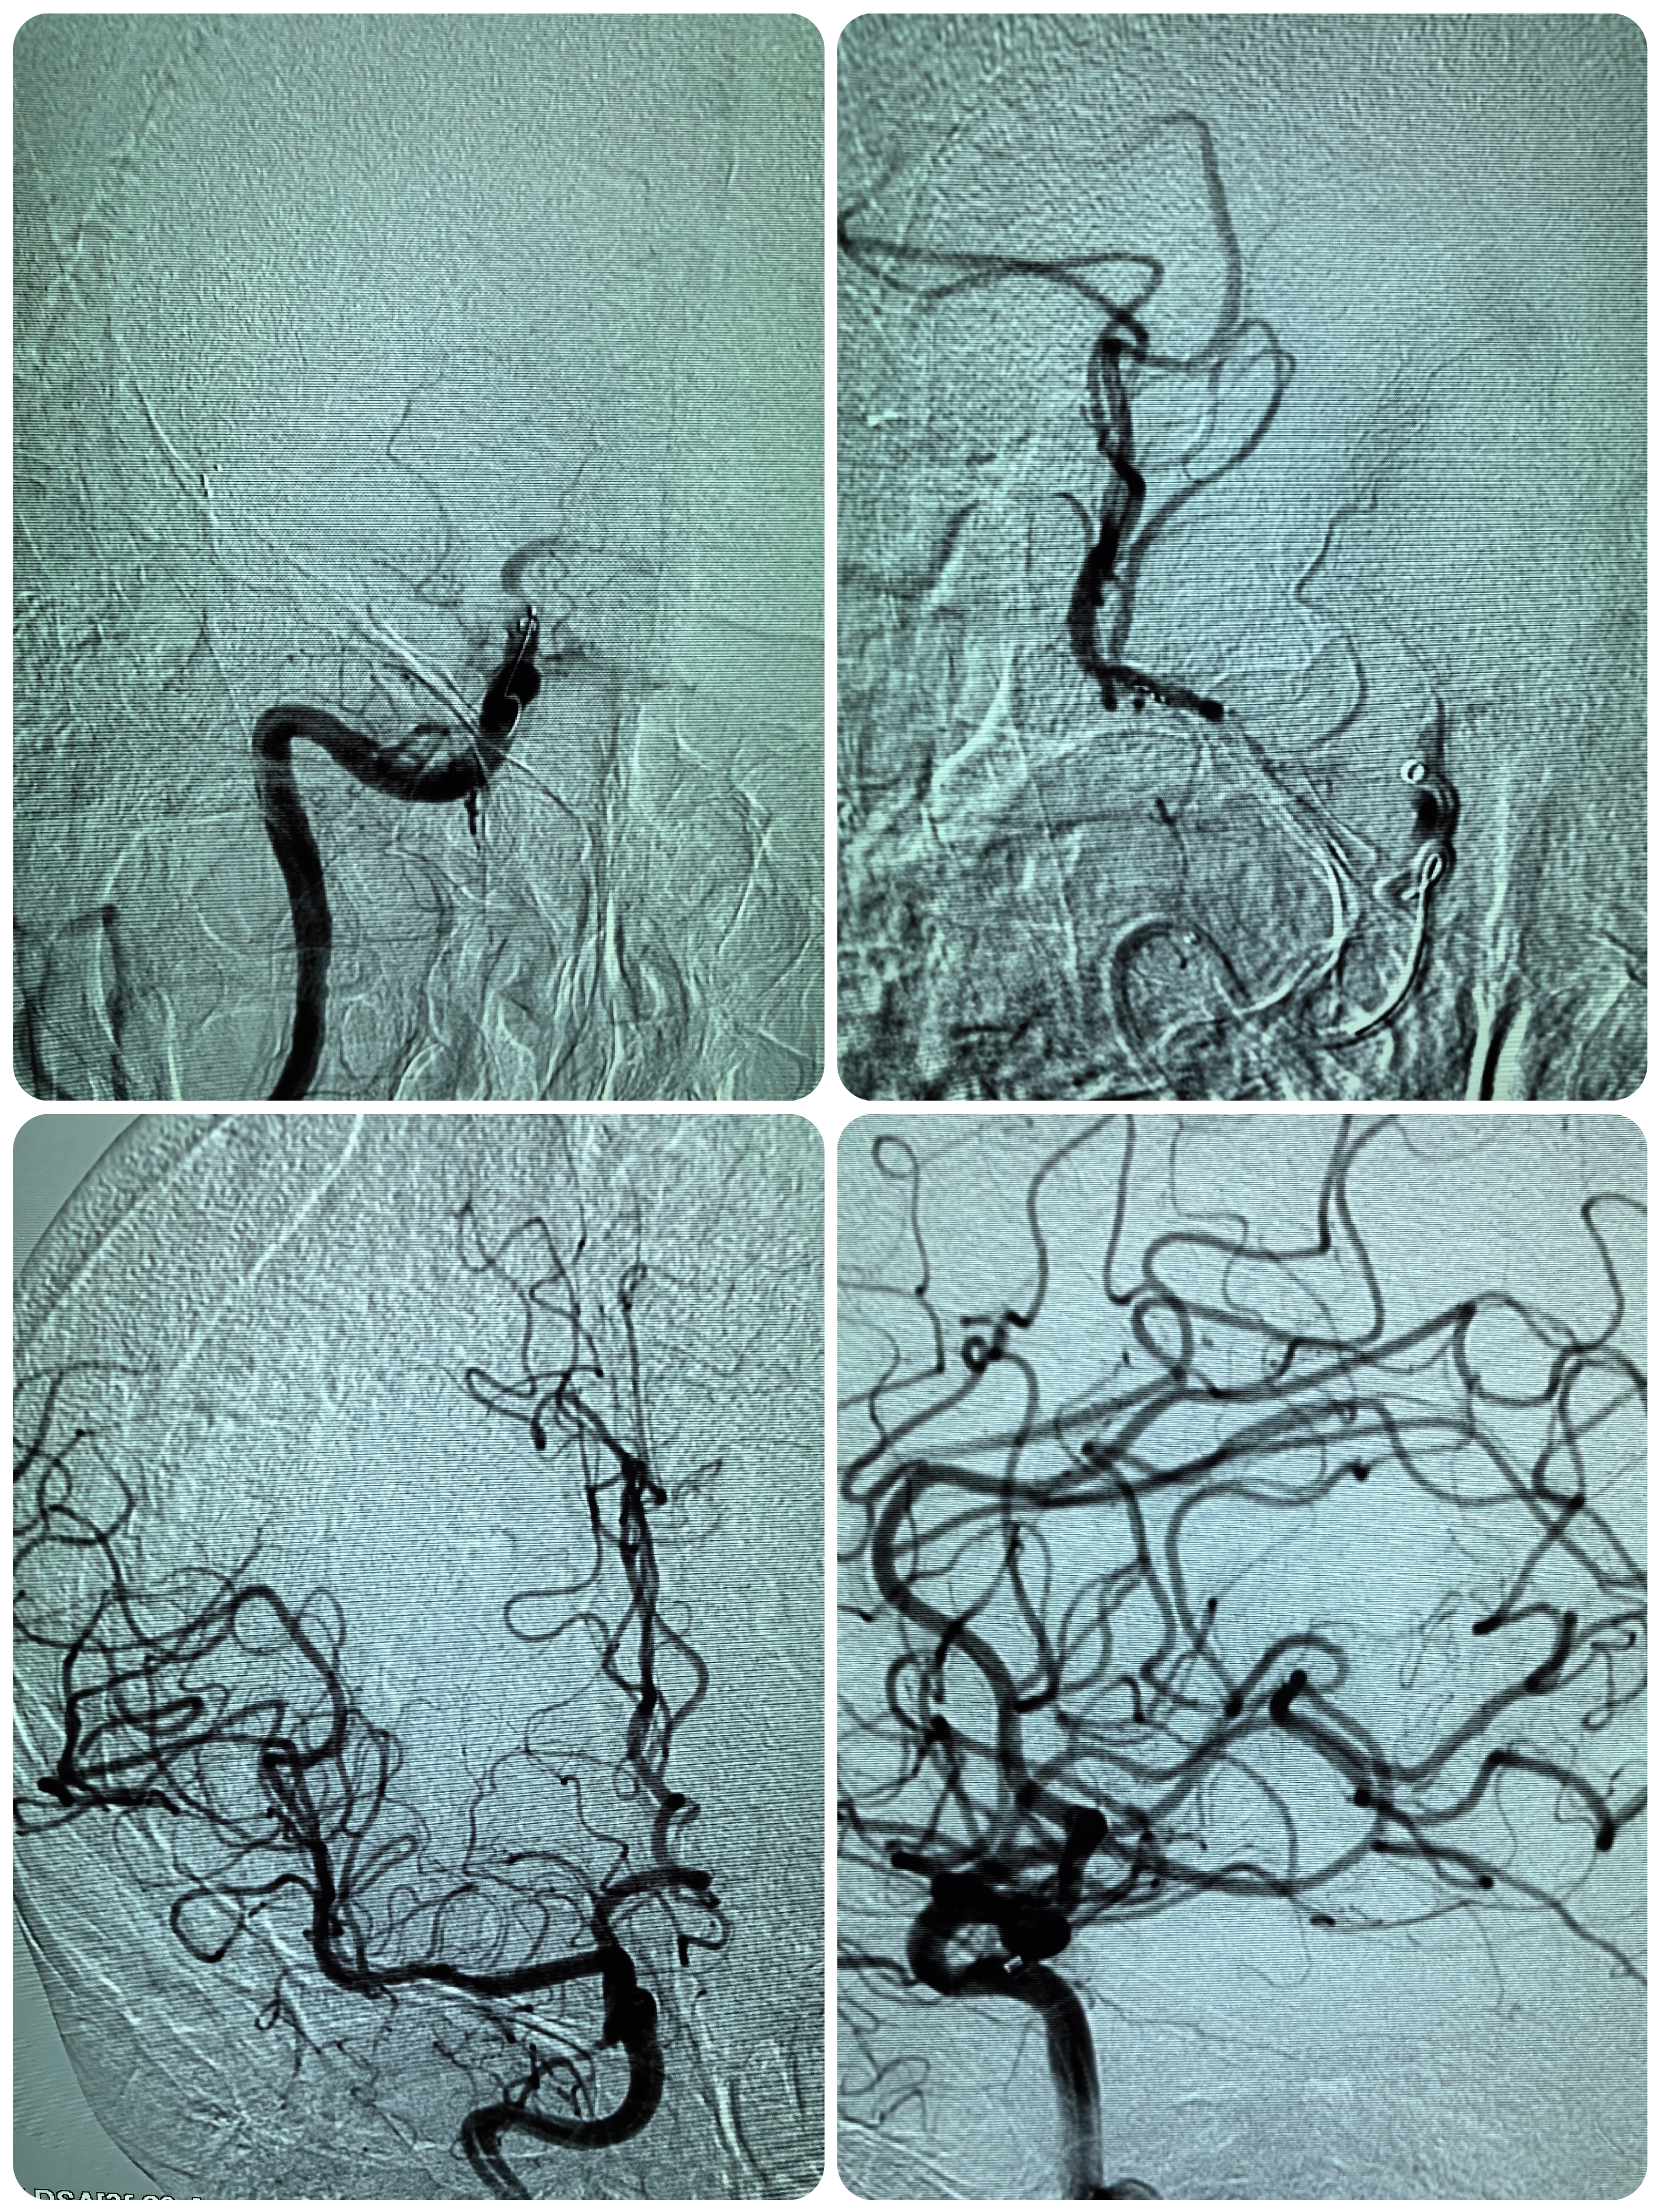

FLAIR序列未见右侧梗死,存在DWI与FLAIR序列不匹配,存在可挽救缺血脑组织,向患者家属详细交代病情及手术风险,家属知情同意后立即桥接血管内治疗。

患者术前明确右侧颈内动脉系统栓塞,遂快速建立8F导引导管+CAT6中间导管取栓路径,微导丝携微导管顺利通过病变。

1、本例患者起病急骤,右侧凝视,左侧偏瘫,CT可见右侧大脑中动脉高密度征,发病2小时,给予静脉溶栓后症状未见缓解,遂桥接血管内治疗。

2、该患DWI显示病灶较大,但FLAIR序列存在不匹配,具备介入治疗指征。

3、SWIM技术有效开通颅内大负荷血栓后应积极预防再灌注损伤,积极控制脑水肿。